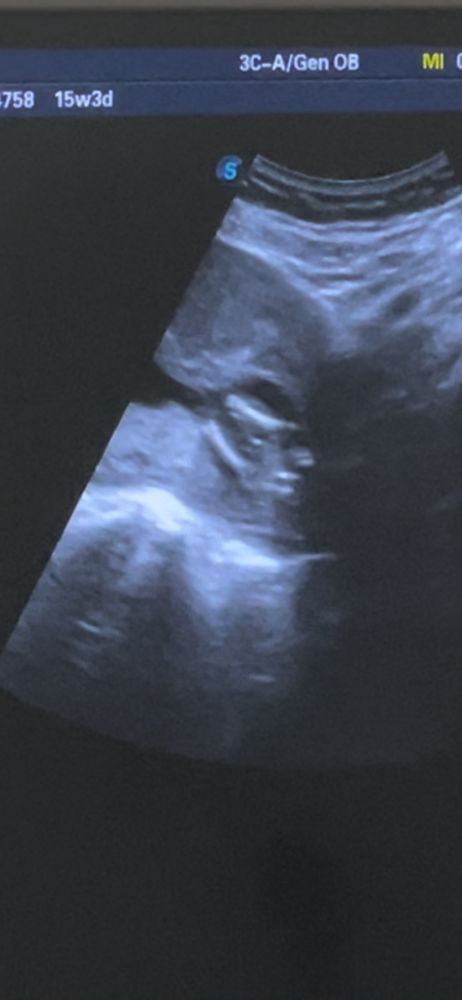

Пол ребёнка

Похоже на девочку)

Видно плохо, но на втором фото вполне может быть девочка, вроде бы видно "кофейное зёрнышко". Но, повторюсь - на этих снимках видно плохо.

Сегодня сказали,что будет мальчик. Закрашиваю кружок ☺️